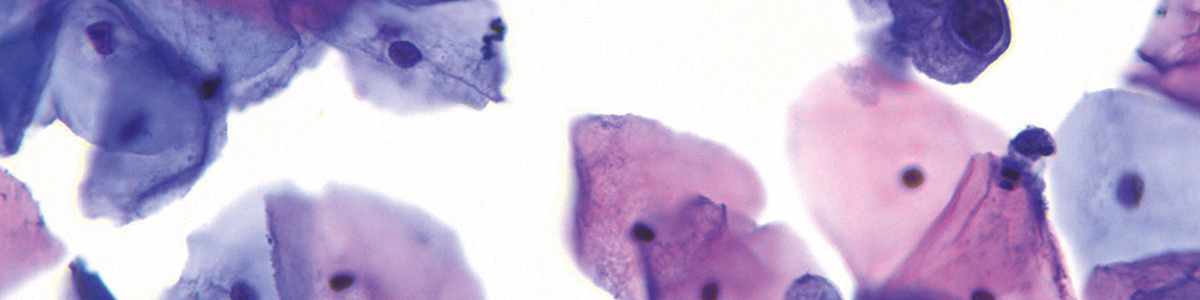

Dünnschichtzytologie ThinPrep®

Die Dünnschichtzytologie stellt eine Weiterentwicklung dieser Methode dar, bei der die entnommenen Zellen in einer Flüssigkeit fixiert und anschließend gleichmäßig aufgetragen werden. Dadurch verbessert sich die Übersichtlichkeit des Präparats. Beide Verfahren spielen heute eine zentrale Rolle in der gynäkologischen Krebsvorsorge und haben dafür gesorgt, dass die Gebärmutterhalskrebsrate in den vergangenen Jahrzehnten dramatisch gesunken ist.